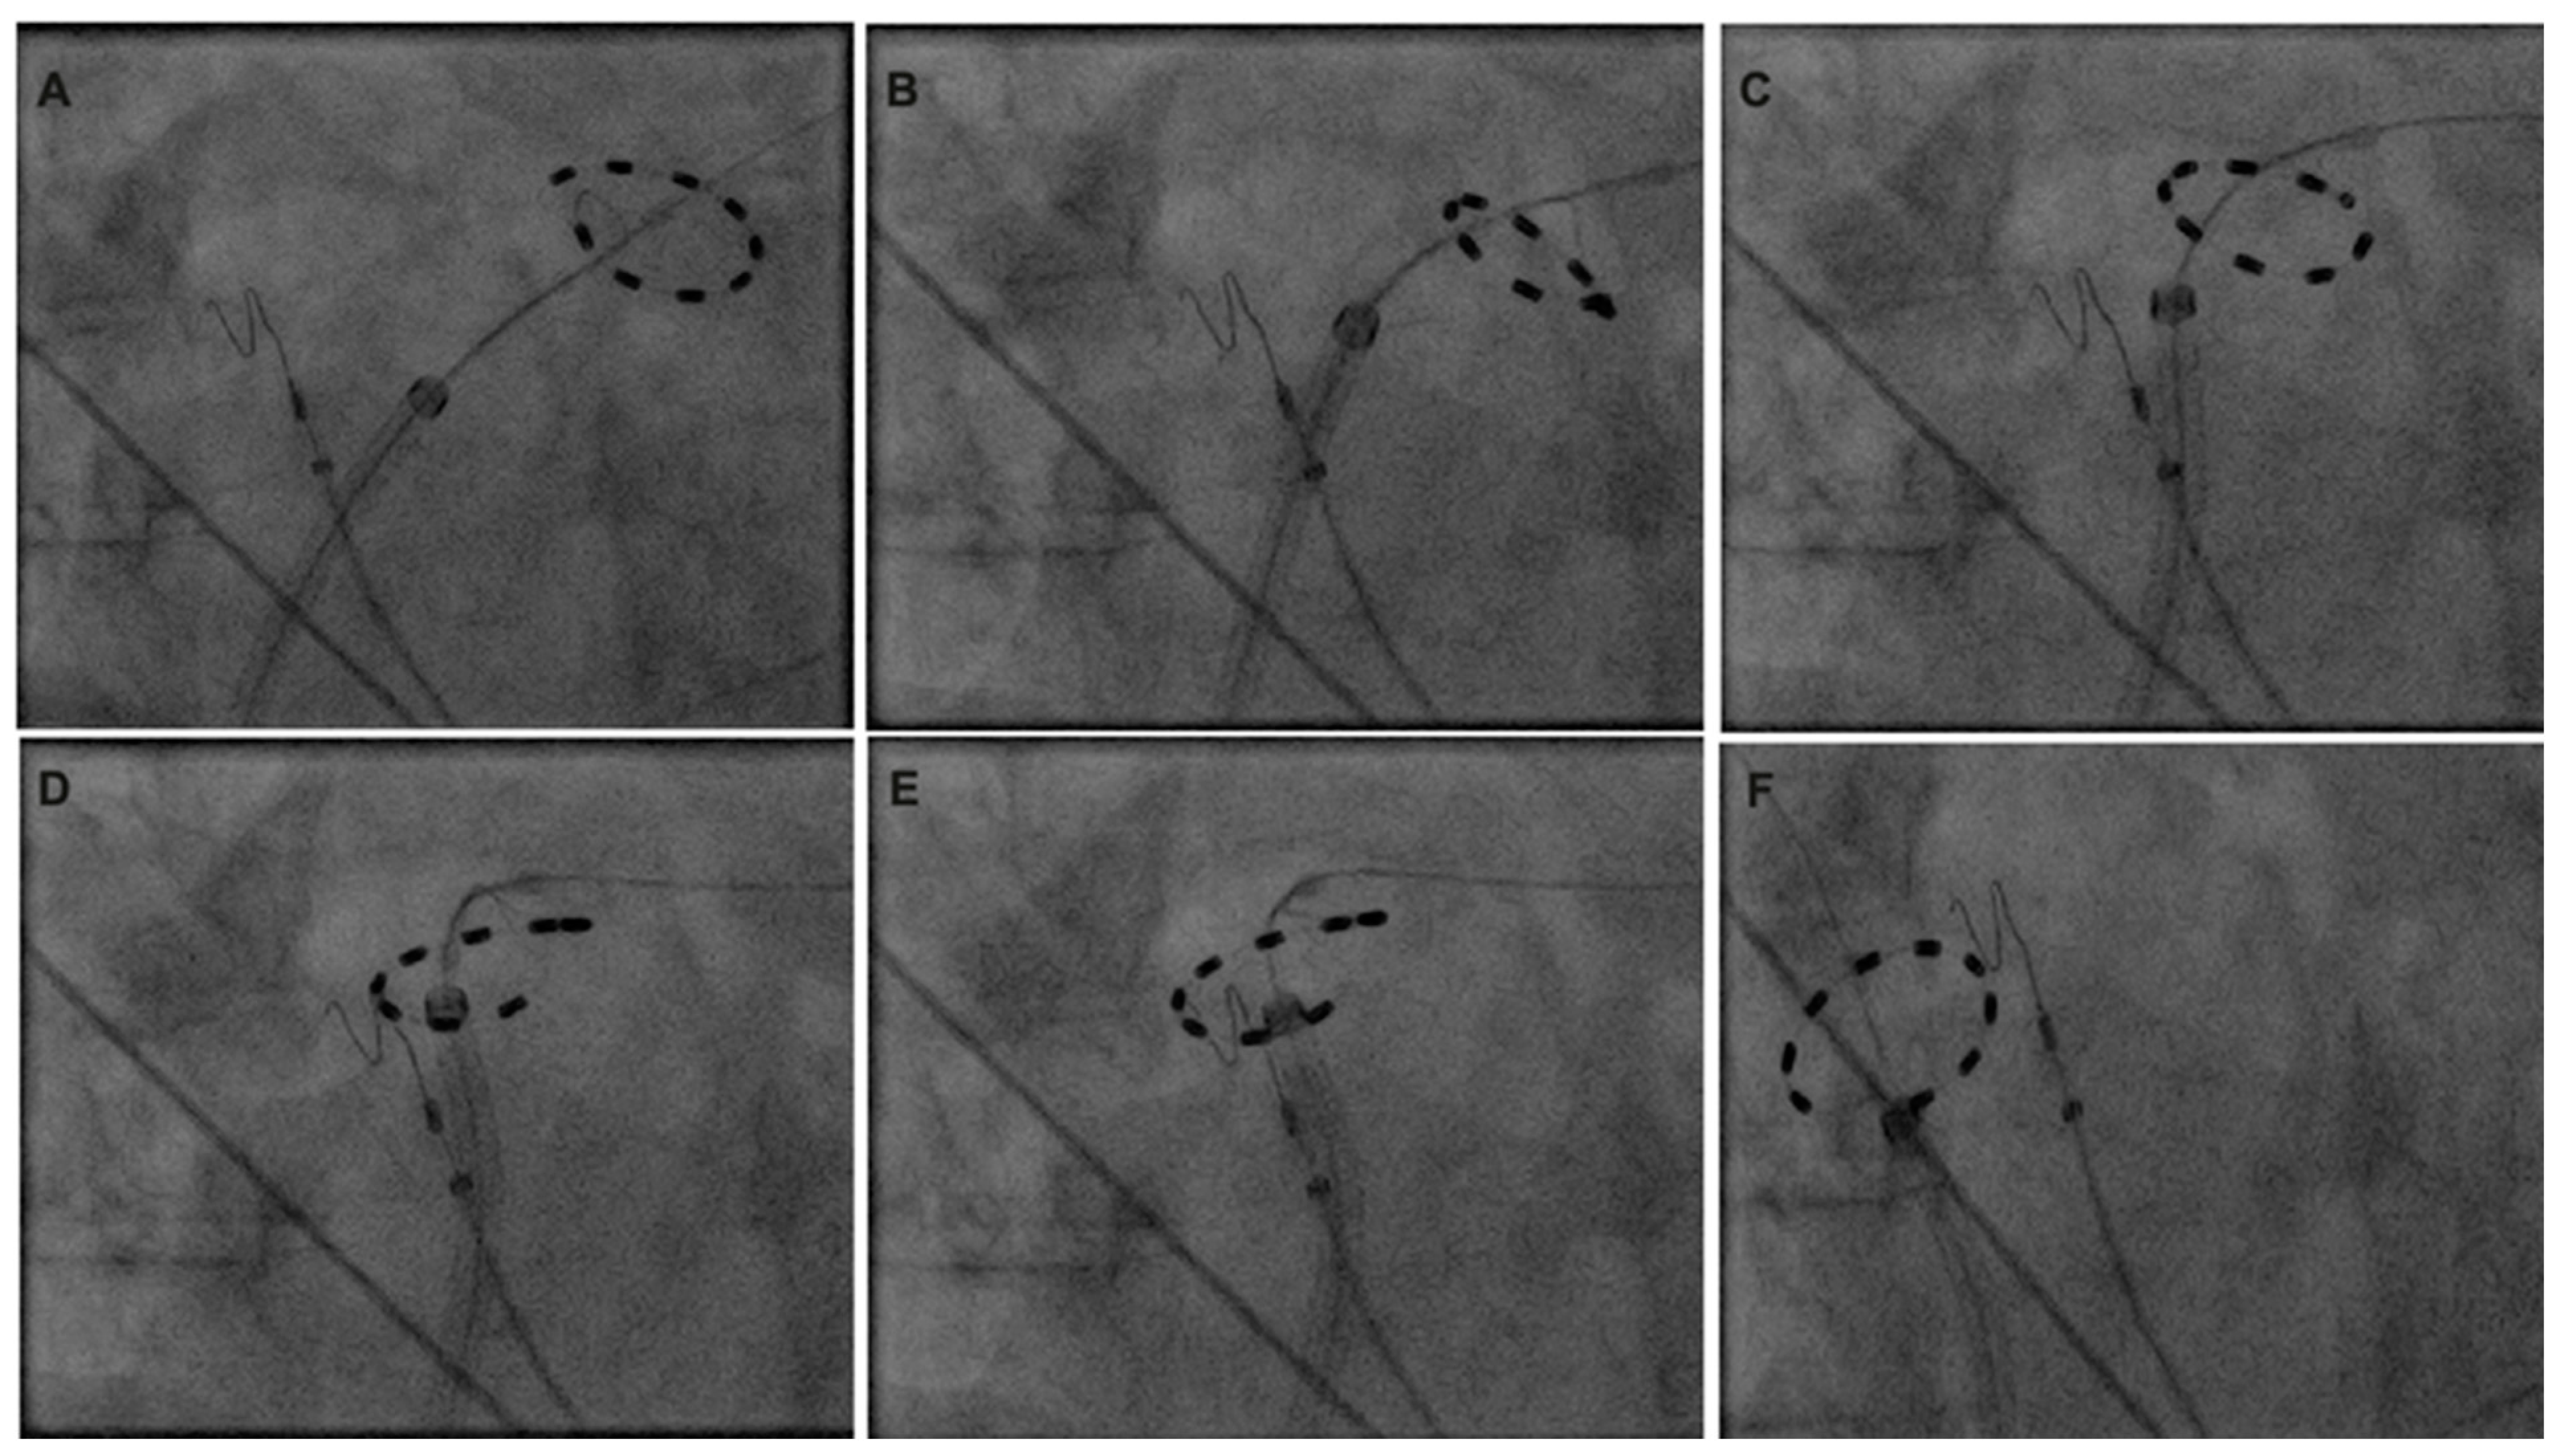

In patients who underwent additional LARA following PVI, the PulseSelect™ catheter was deeply positioned in the left superior pulmonary vein (LSPV) (Figure 1). Sequential overlapping applications were performed along the LA roof, starting near the LSPV isolation site. The PFA catheter was incrementally repositioned by retracting the sheath and slightly rotating the PFA catheter until the isolation position for the right superior pulmonary vein (RSPV) was achieved. The procedural endpoint was defined as complete PVI and conduction block across the LA roof, tested in the sinus rhythm. For patients who continued to experience AF after the initial ablation, electrical cardioversion was performed. Following successful conversion to the sinus rhythm (SR), PVI and LA conduction block were confirmed. The bidirectional block of the LA roof was verified by differential pacing. The PFA catheter was positioned at both the caudal and cranial aspects of the posterior LA wall. Baseline pacing during the SR was conducted at the right atrial upper septum with a cycle length of 500 ms. Activation times at the caudal and cranial positions of the posterior LA wall adjacent to the LA roof were measured. The presence of the LA roof conduction block was confirmed by observing caudocranial ascending activation at the posterior LA wall and a conduction delay of greater than 150 ms next to the ablation area. In patients who underwent PWI, the superior portion of the ablation was performed similarly to the LARA technique. For the inferior part of the LA PWI, ablation began near the left inferior pulmonary vein (LIPV) with overlapping applications, progressing toward the position of the right inferior pulmonary vein (RIPV).

Figure 1.

Maneuvers for left atrial roof ablation with circular pulsed field ablation catheter. (A): Position during isolation left superior pulmonary vein. (B–E): Incremental advancement by slight clockwise rotation and slight sheath retraction for generation of roof line. (F): Position during isolation of right superior pulmonary vein.